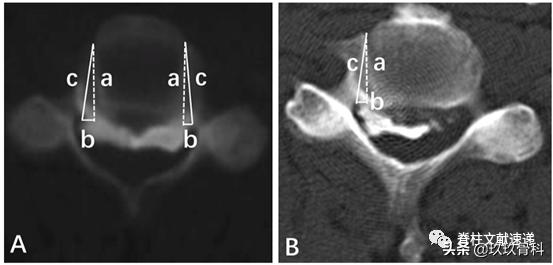

之前提到截骨槽足够宽才能保证ACAF的减压效果,如下图所示,普通开槽沿a虚线进行,遇到宽基底OPLL时须采用c线斜向外开槽才能实现彻底减压。但椎动脉在椎体外侧,开槽过宽椎动脉损伤的风险如何?这篇文献通过尸体和影像学研究进行了评估。

文中通过影像学测量出如下数据

文章认为钩突尖可以作为开槽的解剖标志,开槽后距离横突孔约2mm距离。下图为尸体解剖图片,a开槽线位于钩突尖内侧,b横突孔内缘,c椎弓根内缘投影,神经钩紧贴椎弓根。

从解剖来说,ACAF不易损伤椎动脉,但考虑到解剖变异,术前行CTA检查是有帮助的。作者提出3条避免损伤椎动脉的技巧。1)避免使用粗钻头截骨开槽,2)术中保持中线,参照钩突尖部,3)术中随时探查截骨外壁的完整性,这一步尤其重要。